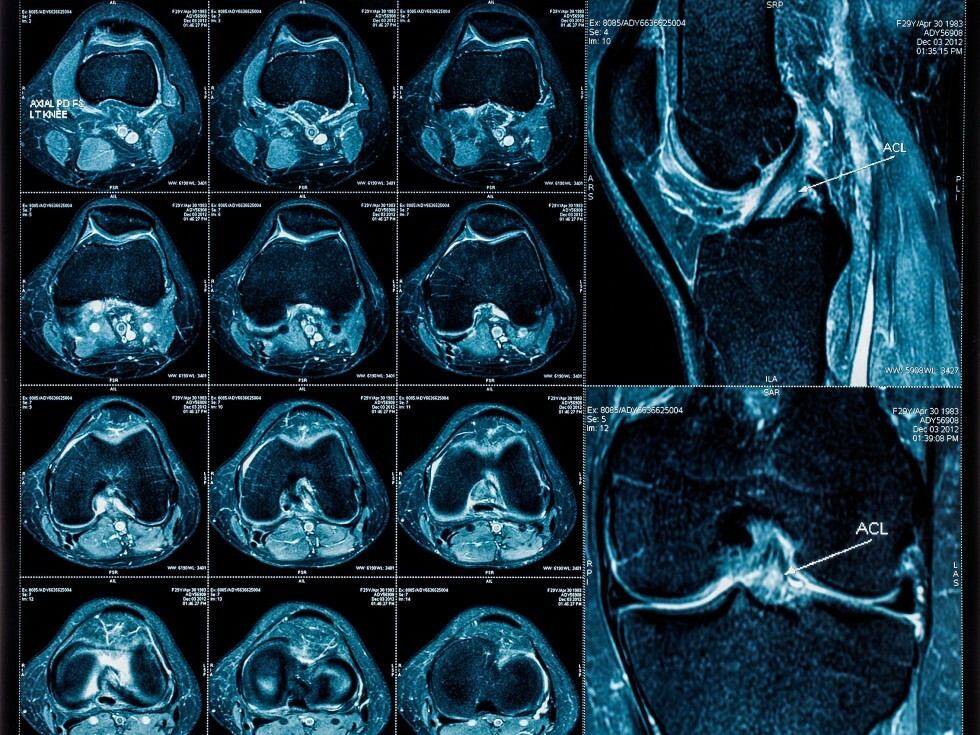

MRI of knee images collage

MRI Knee

Magnetic resonance imaging, or MRI, is a method of producing detailed pictures of organs and body tissues by exposing a patient to radio waves in a strong magnetic field. The field is measured and analyzed by a computer, which forms two- or three-dimensional images that may be viewed on a monitor. Because it uses radio waves and a magnetic field rather than x-rays, there is no exposure to radiation. An MRI can be used to examine every joint in the body. Most commonly the spine, knee and shoulder are viewed, but the procedure also can be performed on the hips, wrists, and hands. An MRI is often the best choice when examining joints because it provides very clear pictures of the soft tissue near and around the bones. The procedure often is used to diagnose sports-related injuries and work-related injuries.

Your doctor may recommend an MRI of the joints or extremities to identify and locate the cause of bleeding, swelling or pain in your bones and muscles. Small tears to muscles, ligaments and tendons also can be detected. An MRI of the joints or extremities can be used to present a clear picture of degenerative disorders such as arthritis. In addition, an MRI of the joints and extremities sometimes is used to identify tumors and infections in the bone and joints and masses in the soft tissue.